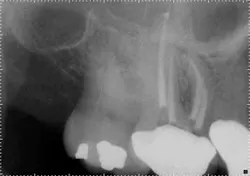

However, when the anatomy is the most complicated with multiple curves or the smallest canals, a different file system might be a better choice (Figs. 3 and 4). Although almost all root canals can be treated with WaveOne, in certain anatomies the root canal procedure is actually easier and more efficient when utilizing a file system that has more tip sizes and taper choices and ultimately requires more files. Vortex Blue (Dentsply Tulsa Dental Specialties), with its incredible resistance to cyclic fatigue and reduced shape memory, is an ideal file choice in this clinical situation. Vortex Blue files have tip sizes ranging from ISO 15-50 and tapers of 0.04 and 0.06. This results in great flexibility to treat the most complicated canal anatomies — flexibility not only in the file itself, but also in the size and taper choices that are available. However, to appreciate the metallurgical advantages of the Vortex Blue files, it may be necessary to spin four or as many as six files per canal.

Fig. 3: Preoperative anatomy of tooth No. 31 shows a double curve in the mesial root canal. The size, length and taper of the root suggest a file system with multiple tip and taper choices would be most suitable.

Fig. 4: A glide path was established with a 15/0.04 Vortex Blue rotary file in conjunction with size 10 hand files. Vortex Blue files were then used in sequence until a final shape of 30/0.04 was achieved in the mesial root and 30/0.06 in the distal root.